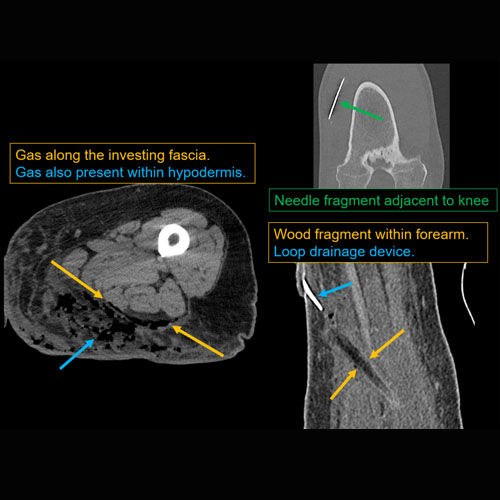

Section 1 Submit Findings CB1118 Findings Limitations There is patient motion or other limitations. Yes No Skin/Hypodermis There is edema or hyperenhancement. Yes No There is soft tissue ulceration or sinus tract. Yes No There is gas or foreign body. Yes No There is confluent hypoenhancement to suggest phlegmon, suppuration, abscess, or drainable fluid collection. Yes No Investing/Intermuscular Fascia There is edema, thickening, or hyperenhancement. Yes No There is hypoenhancement or gas along the fascia. Yes No There is bulging of the fascia. Yes No Muscles There is edema or hyperenhancement. Yes No There is hypoenhancement, lack of enhancement, or organized fluid collection. Yes No There is fatty atrophy. Yes No Bones There are fractures. Yes No There is periosteal reaction, osseous destruction, or focal demineralization to suggest osteomyelitis. Yes No There is cloaca, sequestrum, or involucrum. Yes No There is a subperiosteal or intra-osseous abscess. Yes No Visualized Joints There is a joint effusion. Yes No There is malalignment, degenerative changes, or other gross internal derangement. Yes No Miscellaneous There is tenosynovitis. Yes No Major visualized vascular structures are abnormal. Yes No Major visualized nerves are abnormal. Yes No